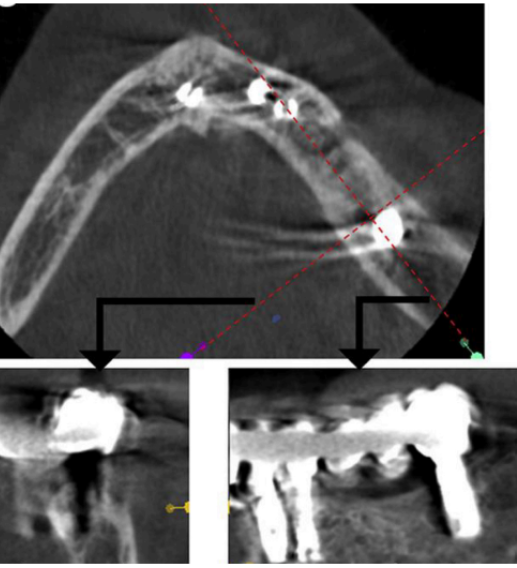

what is this showing for the CBCT

volumetric rendering

bilateral view of TMJ